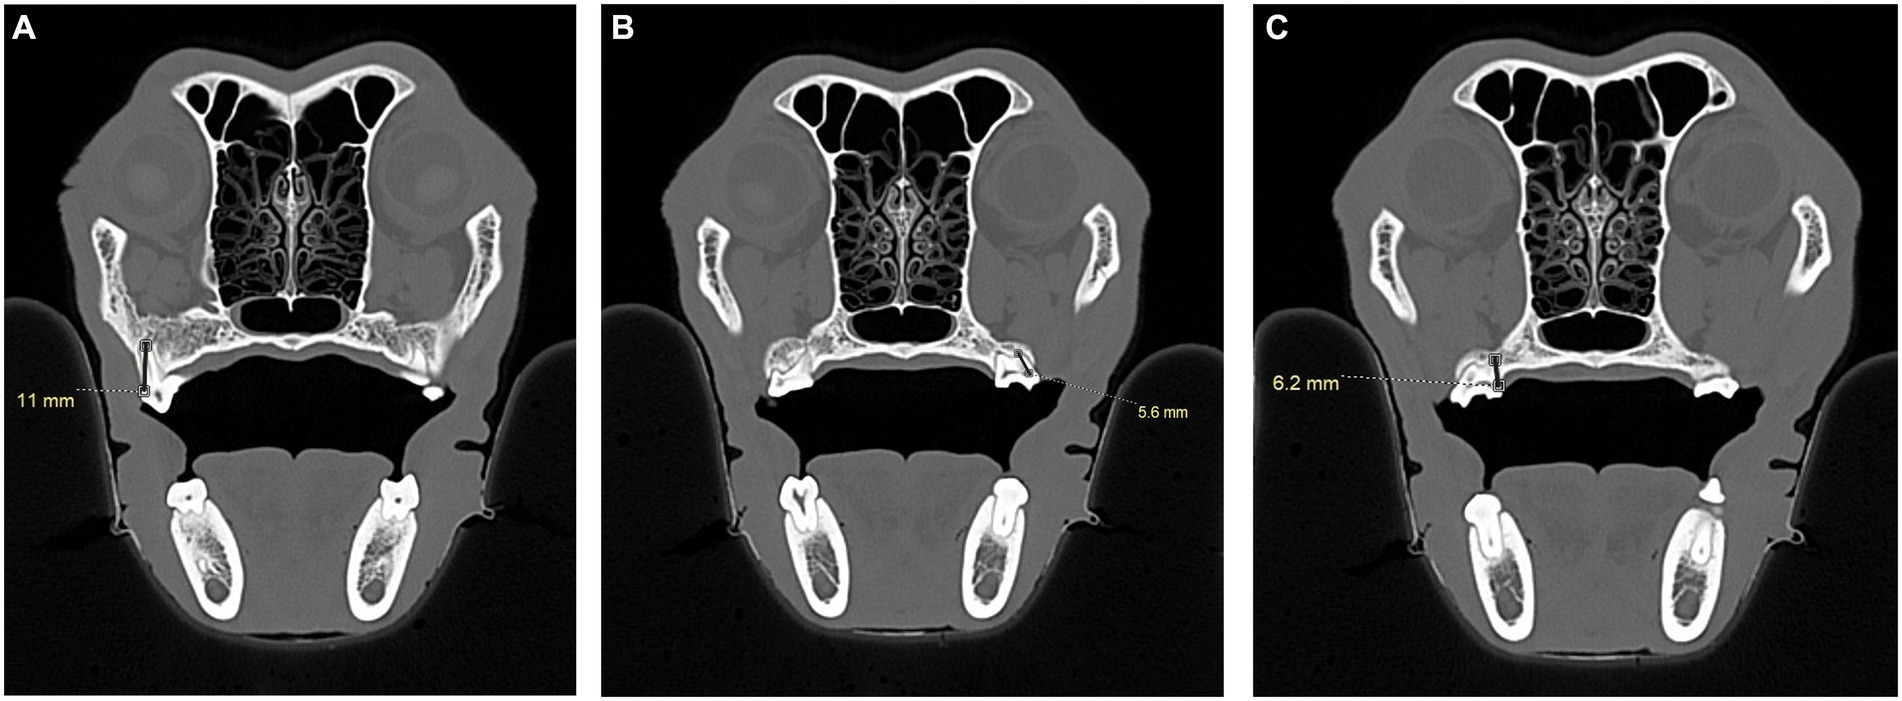

Figure 12

Three-panel CT scan images labeled A, B, and C show transverse views of the nasal cavity and surrounding structures in a dog skull. Panel A measures a distance of eleven millimeters that is measured from the cementoenamel junction, visible as a bump on the side of the tooth, to the root apex of the maxillary first molar tooth in a dog; panel B a measurement of five point six millimeters is taken from the horizontal pulp, visible as a black horizontal line in the crown of the second maxillary molar, to the tip of the distal buccal root. Panel C shows the alternate way root length was measured from the horizontal pulp, visible as a black horizontal line in the crown of the maxillary second molar, to the tip of the palatal root. The palatal root is closer to center then the distal buccal root. A measurement of six point two millimeters is shown.

Figure 12. CT images demonstrating the measurement, in millimeters, of the distal buccal root length of the maxillary first molar tooth and maxillary second molar tooth in a dog. (A) Transverse CT image showing the measurement of the distal buccal root of the right maxillary first molar tooth in a dog. The measurement was taken from the cementoenamel junction to the root apex (black line). (B) Transverse CT image showing the measurement of the distal buccal root of the left maxillary second molar tooth in a dog. The measurement was taken from the horizontal pulp chamber of the crown to the root apex. (C) Transverse CT image of a dog skull showing the alternative measurement of the palatal root of the right maxillary second molar tooth when the entirety of the distal buccal root was not visible on a single slice. Measurements were taken from the horizontal pulp to the root apex (black line).